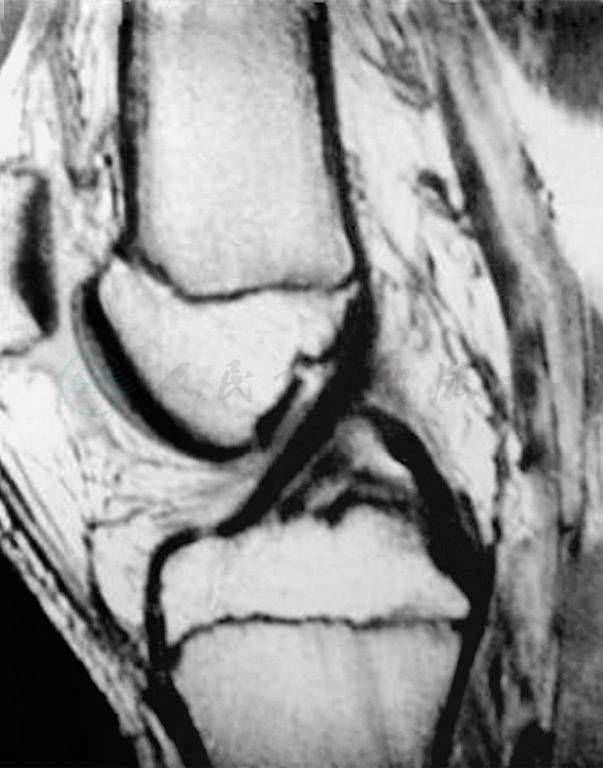

磁共振成像以其优质的图像、对人体的无创性而受到越来越多的重视。磁共振成像应在冠状面和矢状面两个平面上扫描影像,扫描厚度每层3~5mm以获得交叉韧带的低密度影像(图8)。如果影像连续性中断,则可以判断韧带损伤。磁共振成像对于前交叉韧带损伤有很高的诊断价值,它的敏感性92%~100%,特异性89%~97%。

图8磁共振成像正常前交叉韧带影像

前交叉韧带急性损伤最初的磁共振成像表现为T2像的髁间窝血肿,以及韧带纤维的不连续(图9)。另外,在股骨外髁和胫骨平台后方会出现骨挫伤(图10),这种影像在前交叉韧带损伤中有很高的特异性。

图9急性前交叉韧带损伤的磁共振成像表现